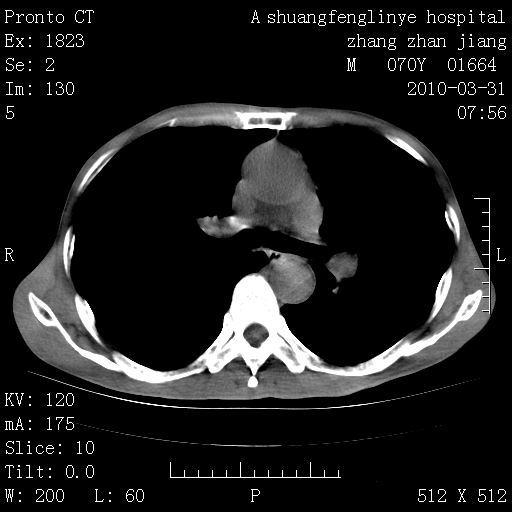

标题: CT25450:肺结核?

双上肺继发型tb并左上空洞形成,主动脉冠脉钙化。

1)两肺上叶继发性肺结核并左肺上叶空洞形成。2)冠状动脉及主动脉钙化。